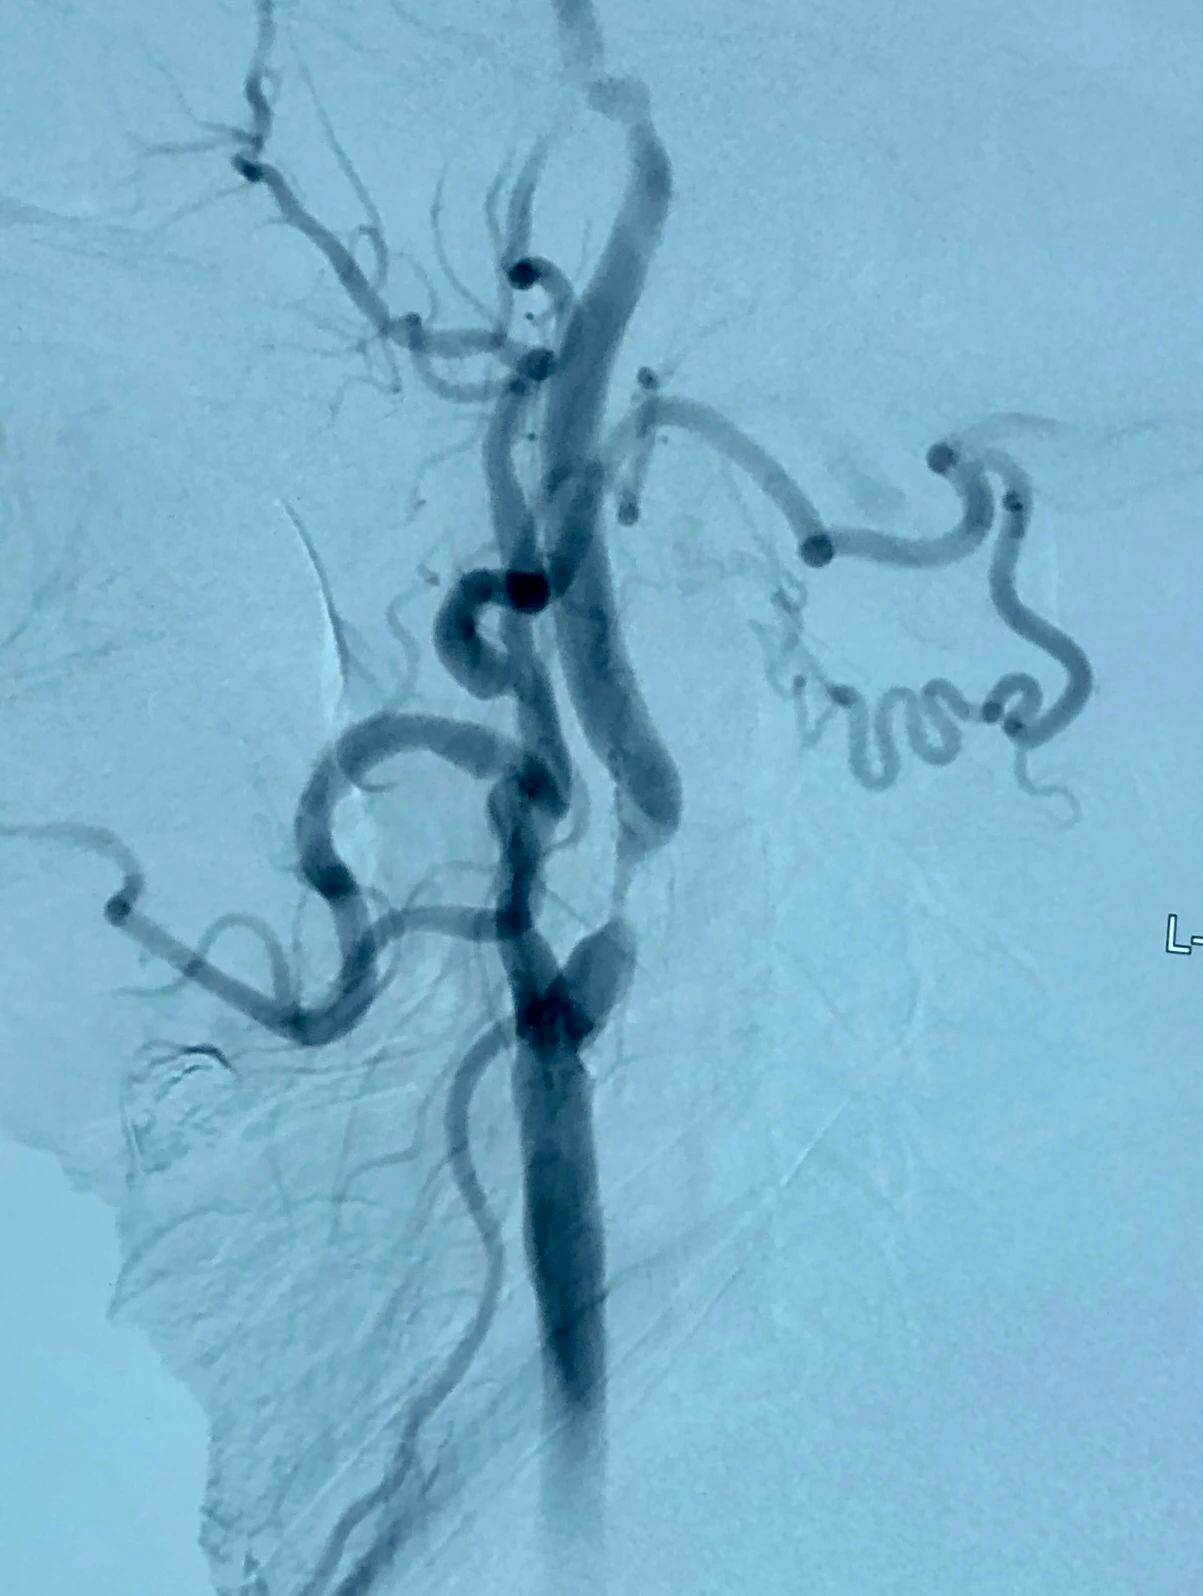

左侧颈动脉支架植入术;

十一个月后,斑块内出血,局部血栓形成,症状性极重度再狭窄;

症状性左侧颈动脉重度狭窄

雅培,锥形支架,6-8*40mm

支架植入术后颈动脉狭窄解除